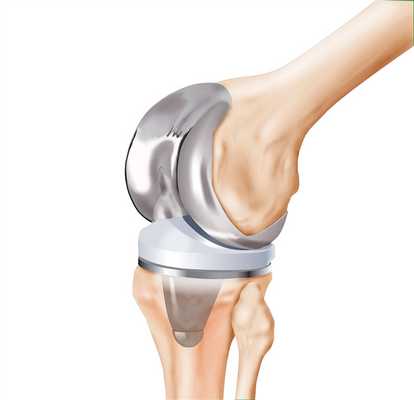

Сегодня эндопротезы коленных суставов выпускаются аногими компаниями в разных странах мира. При желании на рынке можно найти огромное количество первичных, ревизионных, онкологических, тотальных, одномыщелковых протезов. Все они различаются по материалу, строению, способу фиксации и многих других характеристиках. При этом каждый имплант имеет свои преимущества и недостатки.

Эндопротезирование — хирургическая манипуляция, достаточно сложная сама по себе. Но квалификация специалиста, который ее проводит, не единственное требование для успешного результата. Здесь важно еще и правильно подобрать сам эндопротез. Что не так просто, учитывая, как много вариантов предлагает современный рынок: они отличаются по размеру, функциональности, типу фиксации и другим характеристикам.

Выбор эндопротеза коленного сустава — это всегда совместное решение пациента и хирурга, который его консультирует. На современном рынке представлено более 150 видов таких изделий, и некоего общего идеального решения для всех не существует. В каждому случае это решение будет индивидуальным.

Эндопротезы коленного сустава делятся на виды по трем основным признакам — материалам изготовления, типу операции эндопротезирования, для которой они подходят, и способу установки.